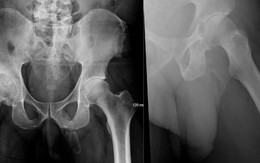

Bệnh cực hiếm: dương vật bị biến thành xương cứng

TTO - Một bệnh nhân nam tuổi lục tuần đến bệnh viện thăm khám sau một trường hợp té ngã và được chẩn đoán dạng rất nghiêm trọng của bệnh Peyronie, là gặp phải hiện tượng "vôi hóa" hoàn toàn trên phần thân dương vật!